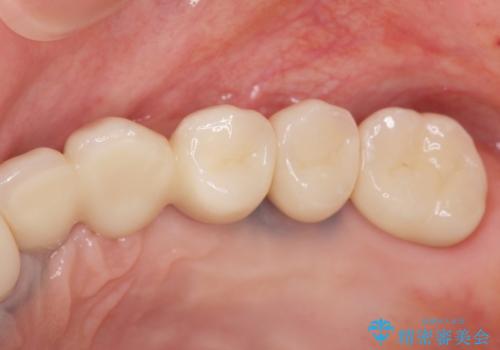

インプラント治療を行ったことでしっかりとした咬合関係を確立することができました。